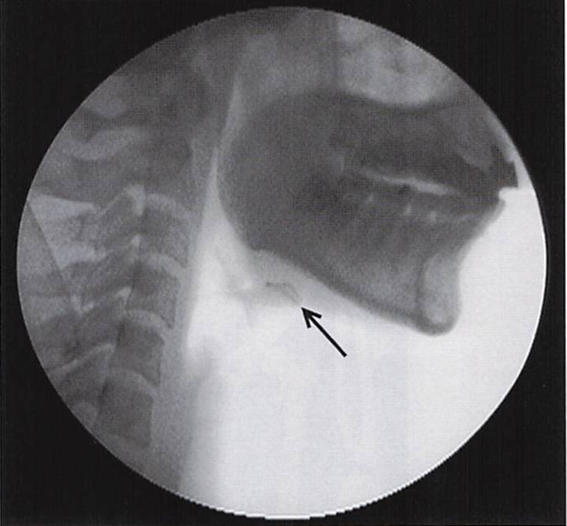

摂食嚥下機能検査中の画像を別に示す。 矢印で示すのはどれか。1つ選べ。

a.舌骨

b.喉頭蓋

c.甲状軟骨

d.披裂軟骨

解答を見る

a